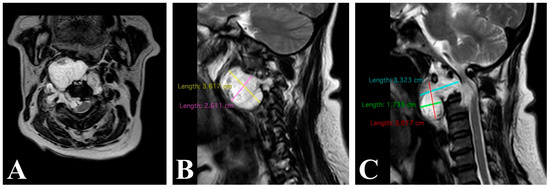

3.1.2. Clinical Case 2

3.1.3. Clinical Case 3

3.3. Surgical Technique and Radiological Follow-Up